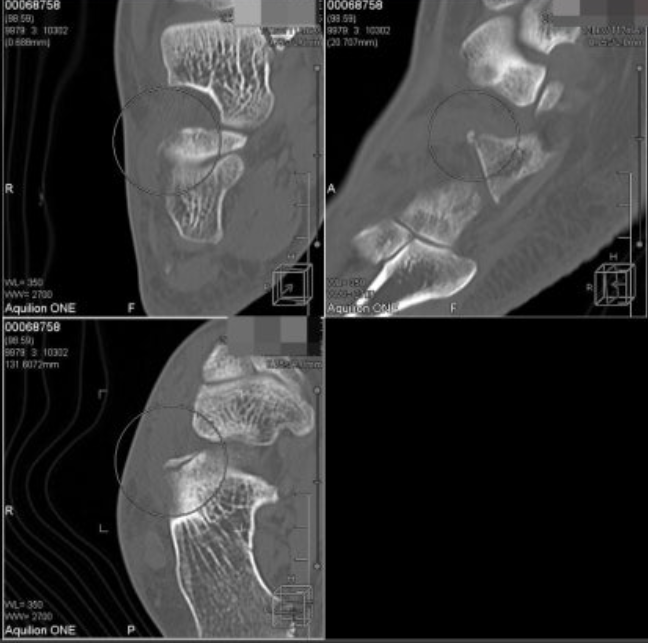

위 환자분은 지하철 계단에서 발목을 접질린 후

X-RAY 검사를 받고 오신 60대 여환입니다.

뼈에는 이상이 없다며

침 한방 맞고자 한의원으로 오셨어요.

발목 바깥쪽 인대들을 쭉 눌러봤을 때

X 표시한 곳에서 심한 통증이 나타납니다.

족소양경근에 프로브를 대어

반대쪽과 비교해보았습니다.

왼쪽 영상을 보시면

이분인대가 늘어나면서

종골 전방돌기(anterior process)가

톡 떨어져 나갔네요.

주변 연부 조직도 부어있어

골절이 의심됩니다.

환자분께 엑스레이에서 잘 안 보이는 부위니

640 CT를 찍어보자고 했습니다.

CT상 급성 골절로 확진되었고

판독서를 근거로 진단서를 발행해서

골절 진단금도 청구하셨습니다.